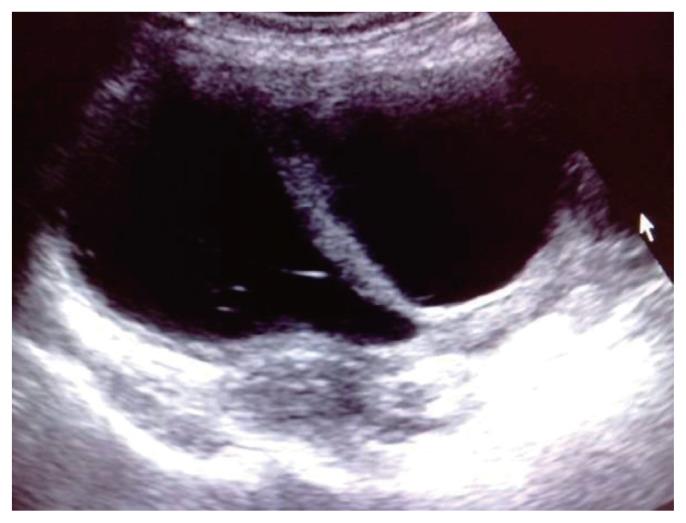

This observational longitudinal prospective analysis of 60 patients was performed over a period of 2 years (2017- 2019). The mean age of the patients was 43.75 years. Ultrasonography of ovarian masses were evaluated, and cancer antigen-125 (CA-125) levels were evaluated. Based on the IOTA classification, the B and M features of adnexal masses were studied. Color Doppler imaging was performed to evaluate the patterns of vascularity and indices.

Sixty patients with 35 benign, 23 malignant, and two borderline lesions were included in the study. In malignant lesions, 17 women (73.9%) were above the age of 45. The CA-125 cut off was ≥35 internatioal units/mL. Based on the IOTA classification, 27/35 (77.1%) benign cases, were correctly identified as benign, 6/35 (17.1%) benign cases were incorrectly identified as malignant, and two (5.7%) were found to be inconclusive. In the malignant group, 17 of the 23 patients were identified as having malignancy. Color Doppler showed three (18.8%) benign tumors had a pulsatality index (PI) of <0.8 and 21 malignant tumors had a PI of <0.8. Four benign tumors had an resistive index (RI) of <0.6 and 100% of malignant tumors had an RI <0.6.

方法

本研究纳入了60例患者,其中35例为良性病变,23例为恶性病变,2例为交界性病变。在恶性病变中,17名女性(73.9%)年龄超过45岁。CA - 125临界值为≥35国际单位/毫升。基于IOTA分类,35例良性病例中有27例(77.1%)被正确鉴定为良性,35例良性病例中有6例(17.1%)被错误鉴定为恶性,2例(5.7%)结果不明确。在恶性组中,23例患者中有17例被鉴定为患有恶性肿瘤。彩色多普勒显示3例(18.8%)良性肿瘤的搏动指数(PI)<0.8,21例恶性肿瘤的PI<0.8。4例良性肿瘤的阻力指数(RI)<0.6,100%的恶性肿瘤RI<0.6。